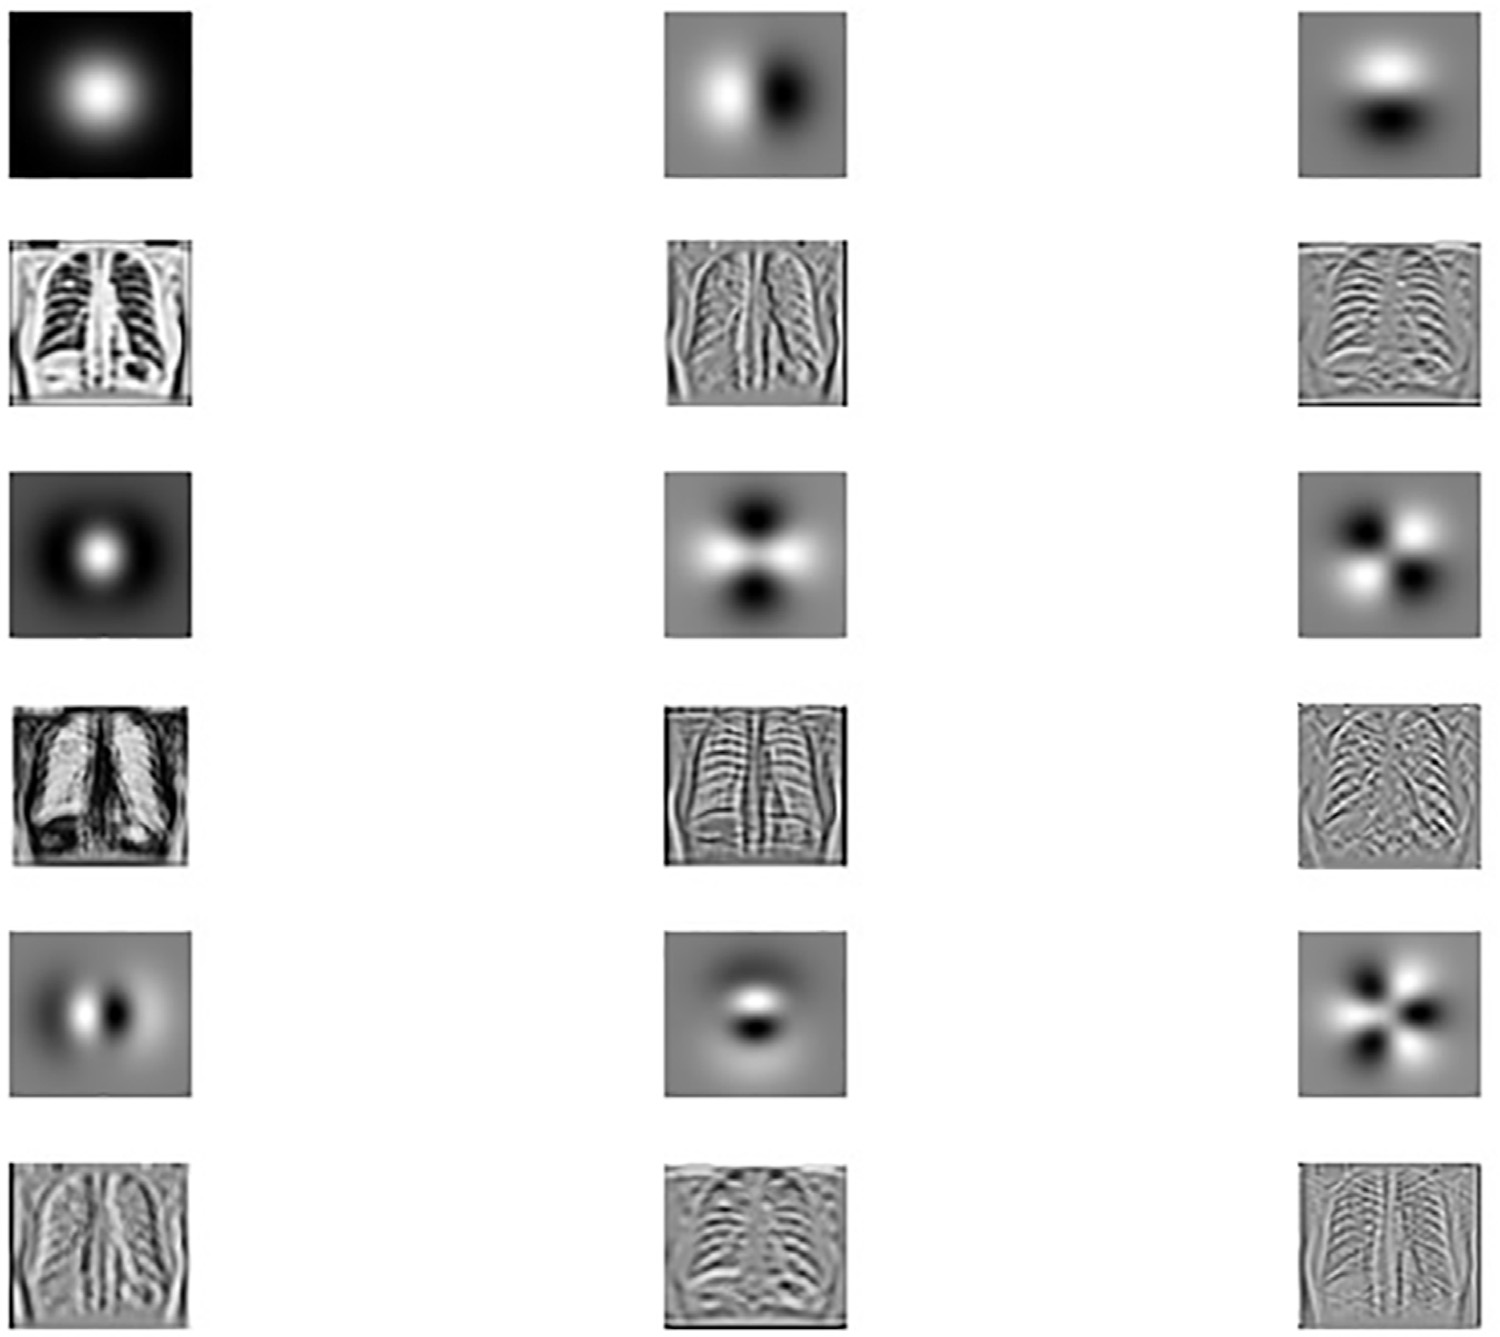

来自JSRT数据库的一组训练图像的前100个基向量,代表X光图像中存在的不同结构。

起始的基向量为低频,中间的基向量代表中频,而从最后的基向量可以明显看出其表示高频内容。

设 A 是由 C 的特征向量构成的矩阵。A 的第一行对应最大的特征值,最后一行表示按降序排列的最小特征值。通常将 C 的这些特征向量称为基函数。在此情况下,即为主成分分析滤波器。通过对给定的胸部X光图像块进行主成分分析训练过程所得到的矩阵 A 在 图14.6 中进行了可视化展示。

图14.7中显示的前两行图14.7对应于低频,能够捕捉图像中的大尺度结构。这些行在很大程度上类似于一阶和二阶高斯导数算子。中间若干行提供了中频滤波器,而最后几行无疑是高频滤波器,且它们与高阶高斯导数算子的相似性显而易见。可以清楚地看出,这些滤波器按照其频率成分具有一定的顺序。通过对给定的X光图像与这些 FIR滤波器逐一进行卷积,将得到图像的主成分,即所谓的主成分图像,如图14.7所示。通过观察这些主成分图像,可以发现第四个主成分图像以肋骨结构为主要特征。

换句话说,在重建过程中,通过从原始图像中减去与肋骨结构相对应的主成分图像来获得去肋骨图像。在本例中,与肋骨结构相对应的主成分图像是基于第四个 PCA滤波器得到的。上述描述可用以下公式表示: